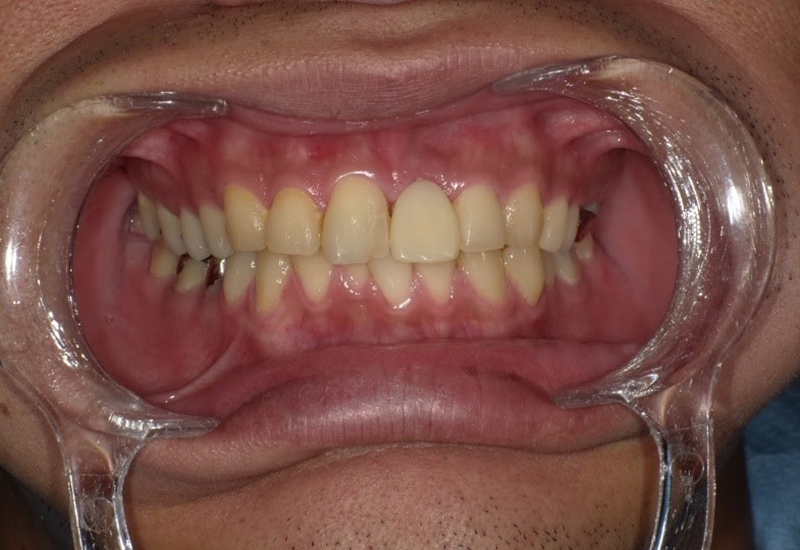

治療前

治療後